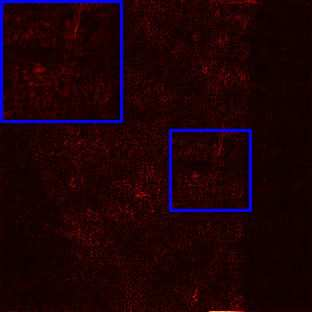

Limited by imaging systems, the reconstruction of Magnetic Resonance Imaging (MRI) images from partial measurement is essential to medical imaging research. Benefiting from the diverse and complementary information of multi-contrast MR images in different imaging modalities, multi-contrast Super-Resolution (SR) reconstruction is promising to yield SR images with higher quality. In the medical scenario, to fully visualize the lesion, radiologists are accustomed to zooming the MR images at arbitrary scales rather than using a fixed scale, as used by most MRI SR methods. In addition, existing multi-contrast MRI SR methods often require a fixed resolution for the reference image, which makes acquiring reference images difficult and imposes limitations on arbitrary scale SR tasks. To address these issues, we proposed an implicit neural representations based dual-arbitrary multi-contrast MRI super-resolution method, called Dual-ArbNet. First, we decouple the resolution of the target and reference images by a feature encoder, enabling the network to input target and reference images at arbitrary scales. Then, an implicit fusion decoder fuses the multi-contrast features and uses an Implicit Decoding Function~(IDF) to obtain the final MRI SR results. Furthermore, we introduce a curriculum learning strategy to train our network, which improves the generalization and performance of our Dual-ArbNet. Extensive experiments in two public MRI datasets demonstrate that our method outperforms state-of-the-art approaches under different scale factors and has great potential in clinical practice.